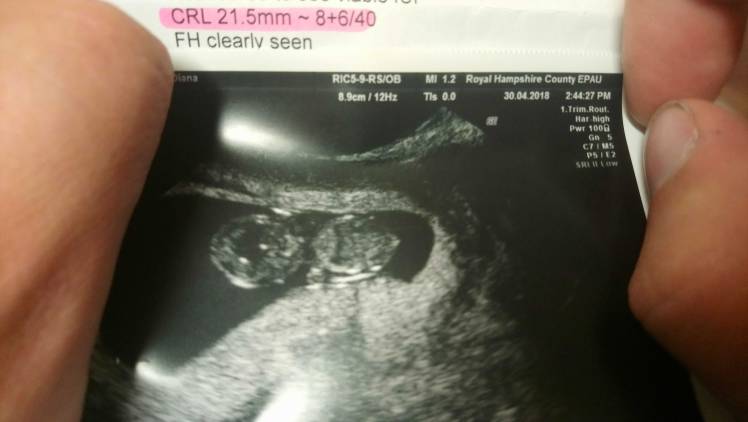

Dziękuję dziewczyny, Jezu ja żadnej nie życzę takich nerwów, jak dziecko się popłakałam na fotelu, mąż patrzył na ekran, ale ja nie chciałam, łzy już rezygnacji mi płynęły same po policzkach, położna delikatnie wsunela głowice, tym razem znowu było wewnetrzne usg, a on do mnie "ona tam jest! Jest tam!" to mu mówię, że najważniejsza jest informacja o akcji serca, a on mi mówi "sama zobacz, serduszko też bije!!" I w tym momencie położna też powiedziała że jest normalna akcja serca. No jak bobr zaczęłam ryczeć, z rozwalonymi nogami przed położna i wylam jak głupia. A one tylko się cieszyły i drukowaly zdjęcia mówiąc jaki piekny przyrost dzidzi, że wzrost o 13mm w ciągu 12 dni to na prawdę piękny wynik.... Ech.... Dobre 5 minut mi zajęło zebrać się z fotela i ubrać tak ryczalam....

Julianna super że wszystko dobrze . Wyobrazam sobie co musiałaś czuć ...bo ja jestem w niepewności...nie wiem czy zabije serduszko u mojego maleństwa ....ten tydzień będzie wiecznością .Chciała bym się wam też pochwalić takimi pięknymi fasolkami .:((((